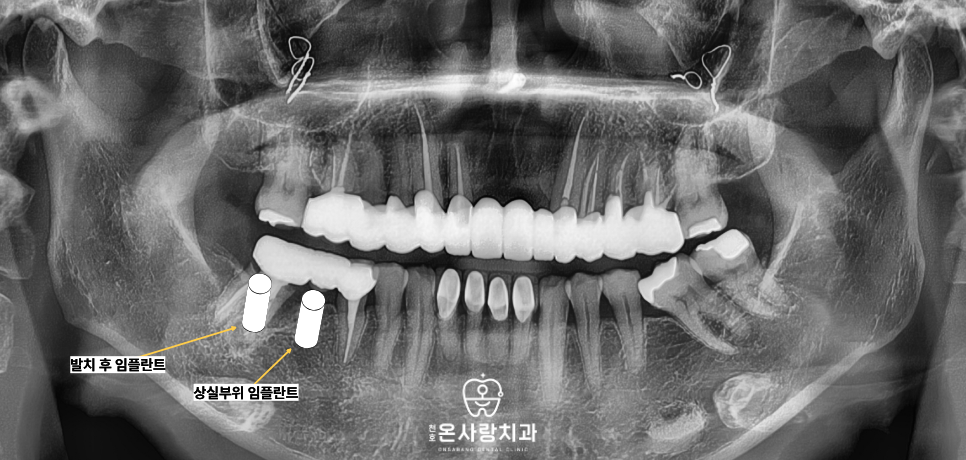

이에 따라 통증의 원인이었던 치아는

발치를 진행하였고 비어 있던 공간인

어금니 위치에 각각 하나씩

총 두 개의 임플란트를

식립하는 계획을 수립하였습니다.

이러한 접근 방식 덕분에

환자분은 불필요한 임플란트 식립이나,

보철물 교체 없이

꼭 필요한 부분만

치료를 받으셨을 수 있었습니다.

남겨두기로 정한 작은어금니는

본래의 건강함을 유지한 채

다시금 제 역할을 다하게 되었고,

그 뒤를 잇는 어금니 부위는

튼튼한 임플란트가 지탱해 줌으로써

전체적인 구강 내의 힘의 균형이

아주 안정적으로 맞추어졌습니다.